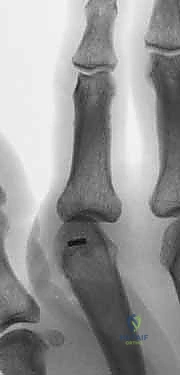

- Plain Radiographs: These are the cornerstone. Obtain posteroanterior (PA), lateral, and oblique views of the affected digit. These are usually sufficient for diagnosis.

- Look for joint space narrowing, osteophytes, subchondral cysts, erosions, and subluxation.

- In psoriatic arthritis, look for "pencil-in-cup" deformities or severe bone resorption (arthritis mutilans).

- Assess bone stock, quality, and size, which are crucial for determining the optimal fixation type.